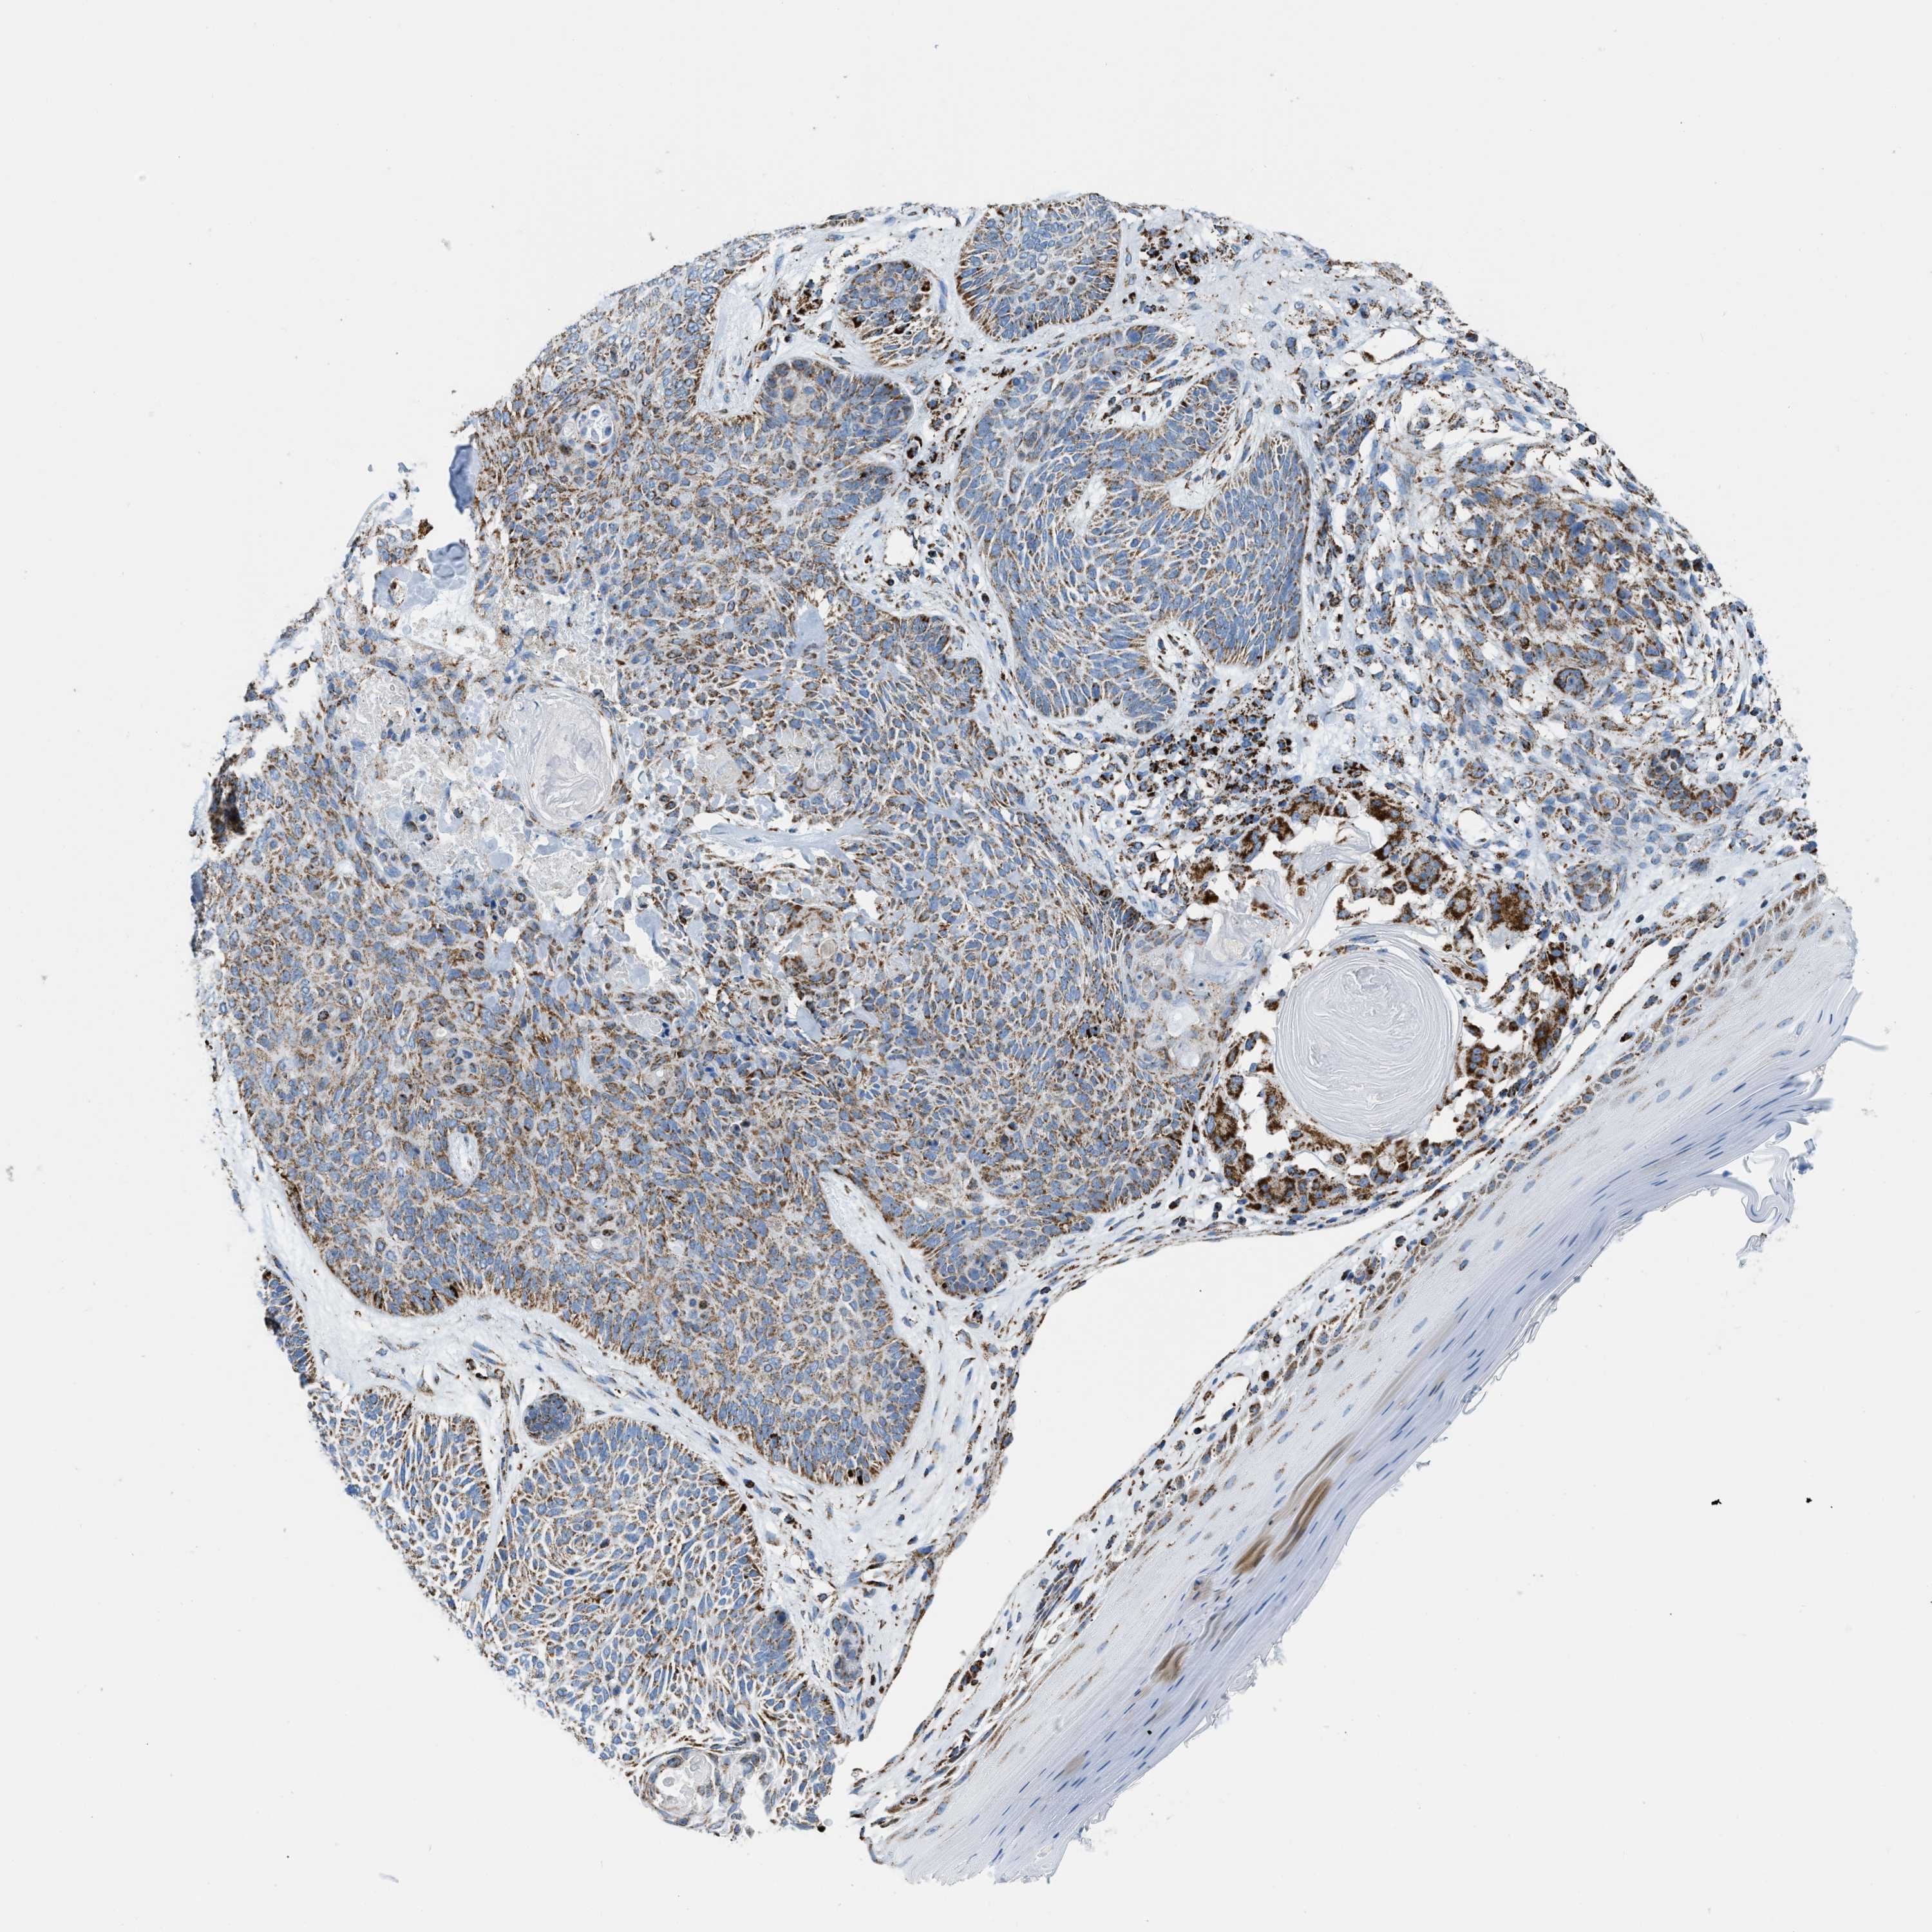

SKIN CANCER - Protein expressioni

A mouse-over function shows sample information and annotation data. Click on an image to view it in a full screen mode. Samples can be filtered based on level of antibody staining by selecting one or several of the following categories: high, medium, low and not detected. The assay and annotation is described here.

Antibody stainingi

Antibody staining in the annotated cell types in the current human tissue is reported as not detected, low, medium, or high, based on conventional immunohistochemistry profiling in selected tissues. This score is based on the combination of the staining intensity and fraction of stained cells.

Each image is clickable and will lead to virtual microscopy that enables deeper exploration of all samples and also displays staining intensity scores, fraction scores and subcellular localization as well as patient and tissue information for each sample.

Antibody HPA018910

Antibody HPA018921

Antibody HPA018923

Staining

High

Medium

Low

Not detected

Intensity

Strong

Moderate

Weak

Negative

Quantity

>75%

75%-25%

<25%

None

Location

Nuclear

Cytoplasmic/membranous

Cytoplasmic/membranous,nuclear

Basal cell carcinoma

Squamous cell carcinoma, NOS

Squamous cell carcinoma, metastatic, NOS